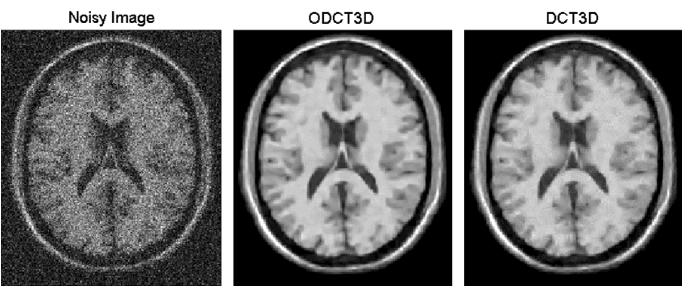

ODCT3D离散余弦变换是一种与傅里叶变换相关的变换,但是一种实数域的变换,可以用于信号与图像的处理,去噪的主要思路为对图像进行离散余弦变换,设置阈值,滤除高频部分,进行噪声的去除。

10.png